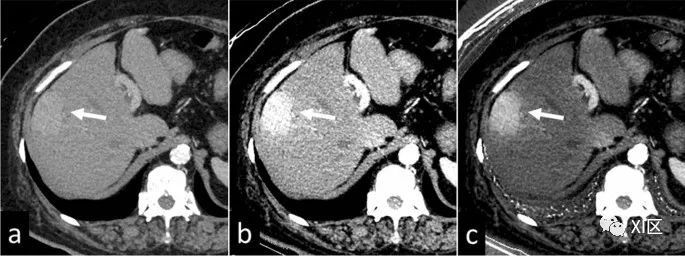

与在低管电压下进行的传统CT扫描一样,碘对比度随着VMI能级的降低而增加;这改善了增强病变的可视化。通过利用这一特性,双能CT扫描产生的40–50 keV的VMI允许对比剂剂量减少40–60%,这对肾功能不全患者尤其重要(图9)。由于某些VMIs上的图像噪声在较低keV设置下会增加,建议采用降噪技术,例如迭代重建。

图9 患有肝细胞癌的64岁女性。由于肾功能不全(eGFR,21ml/min/1.73 m2),动脉期CT图像是以低对比剂剂量(220mgI/kg)获得。在70keV的虚拟单色图像(a)上,肝脏病变的可视化不够充分,而在40keV图像(b)和碘图(c)上可以清楚地检测到。当VMI的能量水平增加(即高于80 keV)时,组织之间的对比度降低,导致金属伪影减少。尽管如此,为了克服密集材料(如金属夹、线圈和支架)产生的严重伪影,可以使用专用的金属伪影减少软件(图10)。